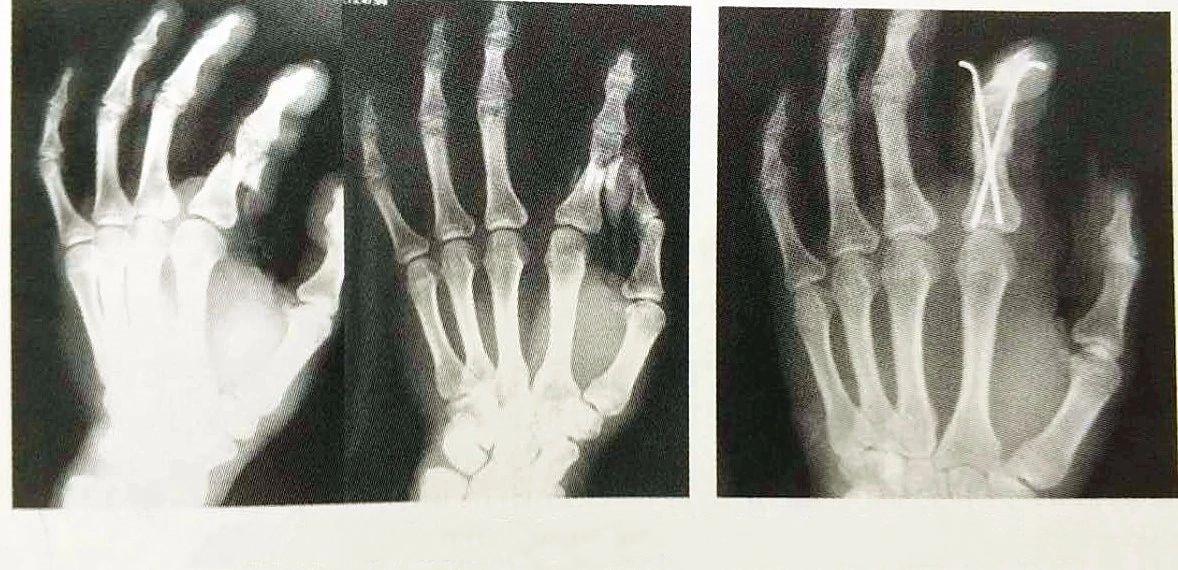

La fixation interne à l'aiguille de Kirschner est appliquée en clinique depuis plus de 70 ans et a été le matériau de fixation interne le plus couramment utilisé pour les fractures métacarpo-phalangiennes, qui est facile à utiliser, économique et pratique, et est la méthode de fixation interne la plus classique, comme indiqué dans la figure 4-15.en tant que fixation interne la plus couramment utilisée pour traiter les fractures de la main, elle est encore largement utilisée.

Il existe de nombreux matériaux de fixation interne pour les fractures métacarpo-phalangiennes, tels que les broches de Kirschner, les vis, les plaques et les cadres de fixation externe, parmi lesquels les broches de Kirschner et les microplaques sont les plus couramment utilisées.Pour les fractures métacarpiennes, l'ostéosynthèse par microplaque présente des avantages évidents par rapport à l'ostéosynthèse par broches de Kirschner et peut être préférée ;pour les fractures des phalanges proximales, la microplaque est généralement préférée, mais lorsqu'il y a des difficultés à placer des vis dans le segment distal des fractures des phalanges proximales et de la tête, la fixation interne avec des broches de Kirschner croisées est préférée, ce qui est plus propice à la récupération fonctionnelle de l'affecté doigt;pour le traitement des fractures de la phalange moyenne, les broches de Kirschner doivent être préférées.